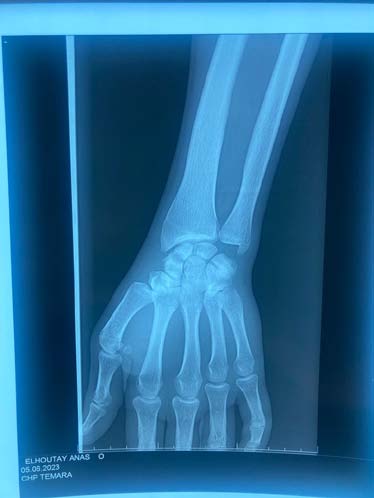

The standard radiographic assessment revealed a scaphoid fracture with an underlying gap, suggesting the possibility of a cyst or pseudarthrosis of the scaphoid (figure 1). The wrist CT scan confirmed the scaphoid fracture with a probable intraosseous cyst (figure 2). The patient underwent surgery via an anterior approach. Careful curettage of the cavity was performed after distraction of the fracture site. The bone defect was filled with autologous cancellous graft harvested from the lower metaphysis of the ipsilateral radius. Fracture stabilization was achieved with 2 pins (figure 3). The histopathological examination of the curettage specimen showed that the cyst wall was lined with flattened fibroblastic cells resembling synovial cells, without true epithelial appearance. There was no mucoid degeneration or myxoid transformation. The patient was immobilized for 2 months in a resin splint. After this period, the hardware was removed under local anesthesia. Several sessions of functional rehabilitation were initiated after plaster removal. At the latest follow-up at 6 months after treatment, the patient had regained good wrist function, with painlessness and resumption of leisure and professional activities.

From a radiological perspective, typical images show osteolytic lesions of a few millimeters in diameter, either solitary or multilobulated, accompanied by a peripheral rim of osteosclerosis [7]. This description corresponds to the lesion observed on our patient's radiographs, along with a discontinuity at the scaphoid neck, indicating a pathological fracture due to weakening of the scaphoid neck. Computed tomography, whether performed with or without contrast agent injection, allows for precise determination of the nature of the intracystic contents and any cortical involvement [1,7]. It also helps establish a surgical protocol by specifying the most appropriate approach, including the preferred surgical access route.